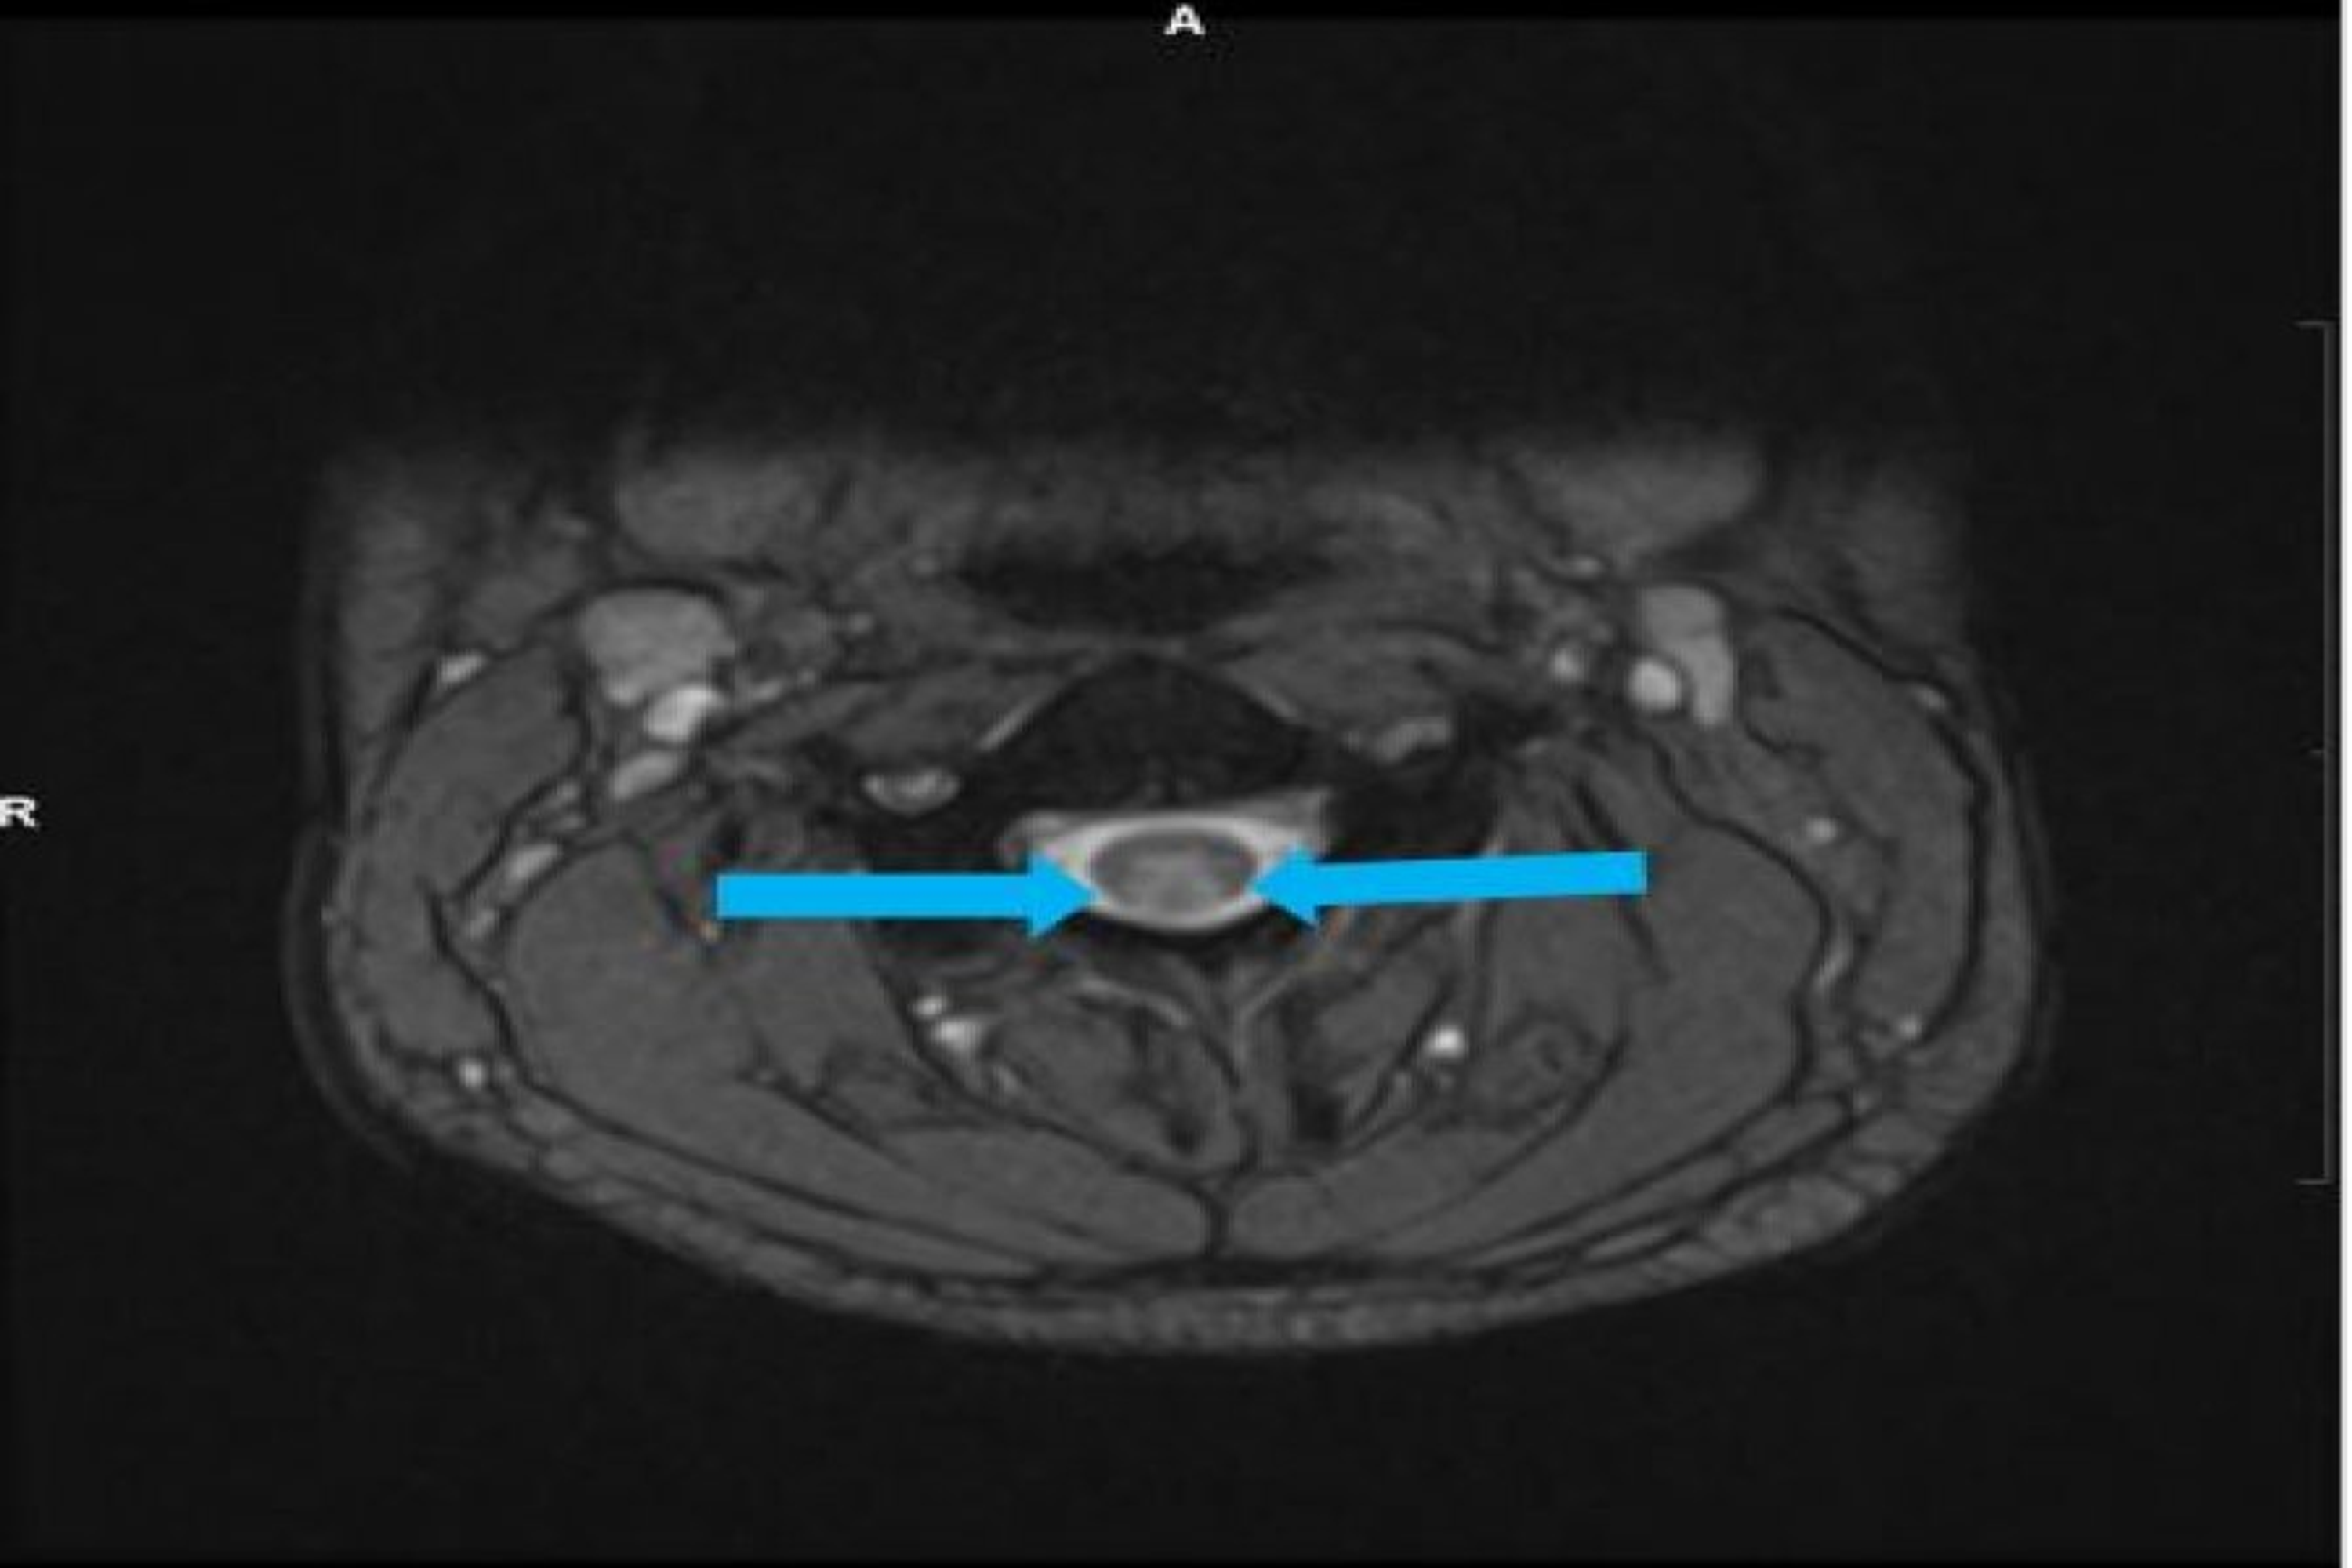

Figure 1 from Nitrous OxideInduced Cervical Myeloneuropathy involving

Figure 1 from Nitrous OxideInduced Cervical Myeloneuropathy involving Does Nitrous Oxide Deplete B12 The recreational use of nitrous oxide (n 2 o) as “laughing gas” is a growing problem. Nitrous oxide, primarily used in the medical field and in the food industry, can cause symptoms of euphoria and analgesia. In this paper, we present a case series of eight patients and discuss the diagnostic challenges and treatment options for vitamin b 12 deficiency. Does Nitrous Oxide Deplete B12.